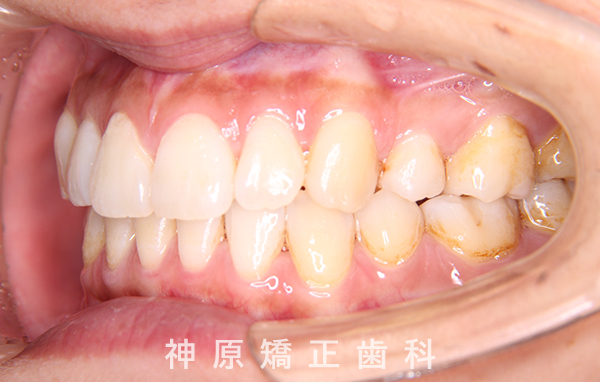

治療終了

治療前と治療後